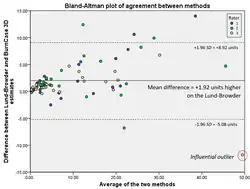

Authors: Kyung tak Yoo, Gowoon Woo, Tae Young Jang, Jae Seok Song

Objective: Measure time required to determine total body surface area (TBSA) burned (%TBSA) using the Lund-Browder chart and BurnCase 3D®, and calculate discrepancy between the two methods' %TBSA estimates. [...] Methods: We asked 3 burn experts with 7 to 9 years of experience to participate in our experiment by estimating TBSA burned (%TBSA) for 26 subjects with a total of 262 photos, based on the Lund-Browder chart and the BurnCase 3D. We also measured time required for each estimation. Results: Estimations via the Lund-Browder chart and the BurnCase 3D showed statistically significant differences for Observers 1 and 2 (p < 0.05), but not for Observer 3 (p = 0.11). Inter-observer variability was insignificant among the observers (p = 0.31). When using the BurnCase 3D, burn estimation was consistent across the 3 participants (p = 0.31), yet the time spent for each method was significantly different (p < 0.05) from using the Lund-Browder chart and the time spent for estimation did not statistically vary (p = 0.20). Time spent on burn estimation varied when using either the Lund-Browder chart or the BurnCase 3D for all participants (p < 0.05). Conclusion: Using the BurnCase 3D over the Lund-Browder chart produced slightly different estimations for TBSA burned but estimation results stayed stable across inspectors. Due to the small sample size however, further investigation is necessary. doi: 10.15347/WJM/2020.002